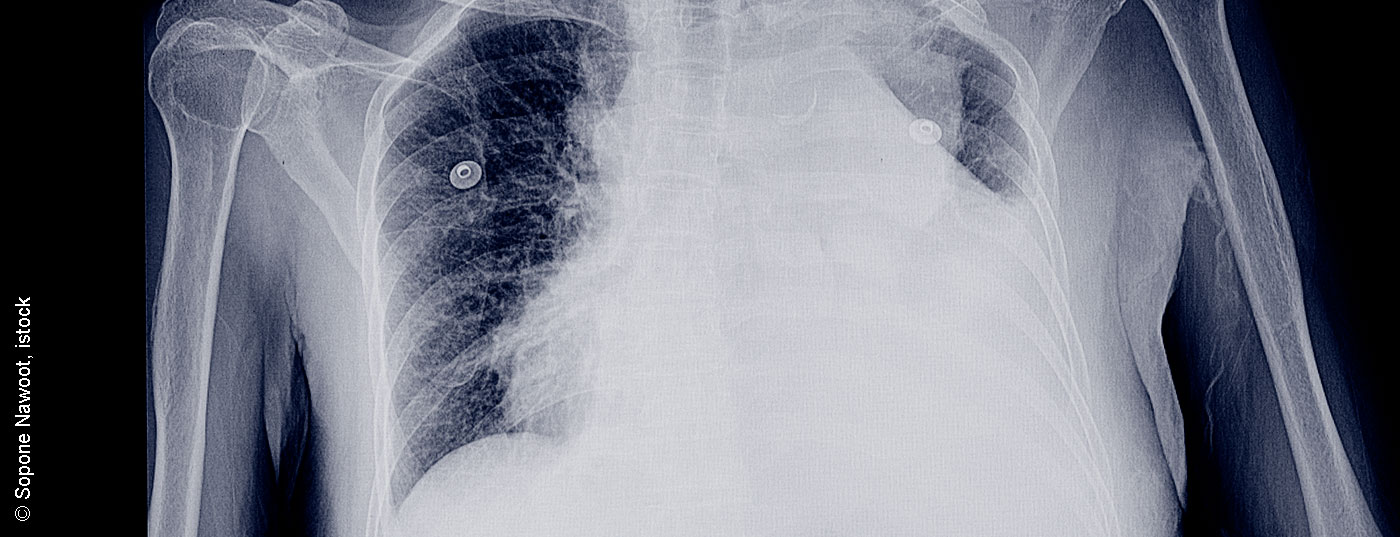

pleuraerguss_istock-952689296

• Pleuraerguss

Vom sinnvollen diagnostischen Algorithmus zur Guideline-konformen Therapie

Die Diagnose des Pleuraergusses ist sehr komplex, da eine Vielzahl von Krankheitsbildern einen Pleuraerguss verursachen kann. Die wichtigste Unterscheidung ist zwischen trans- und exsudativen Ergüssen und deren Ursachen. Hier helfen laborchemische Parameter und zytologische Untersuchungen. Je nach Ursache kann die weitere Therapie eingeleitet werden. Hierbei stehen neben der einfachen Entlastungspunktion, über Pleuradrainagen bis zur Thorakoskopie zahlreiche Methoden zur Verfügung.